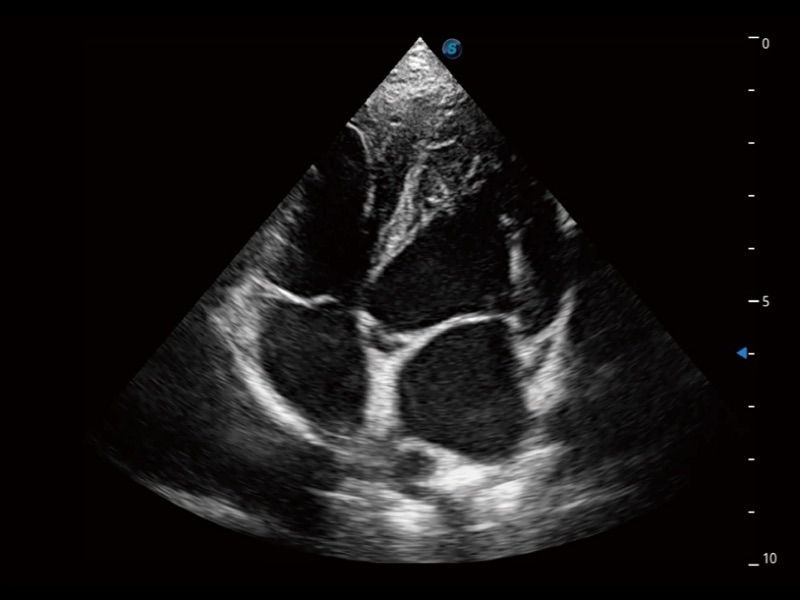

通過360度任意調(diào)節(jié)3條M型取樣線,在同一心動周期上觀察心臟不同位置的運(yùn)動曲線,得到準(zhǔn)確的心功能測量數(shù)據(jù),有效評估心肌運(yùn)動及左心室功能。